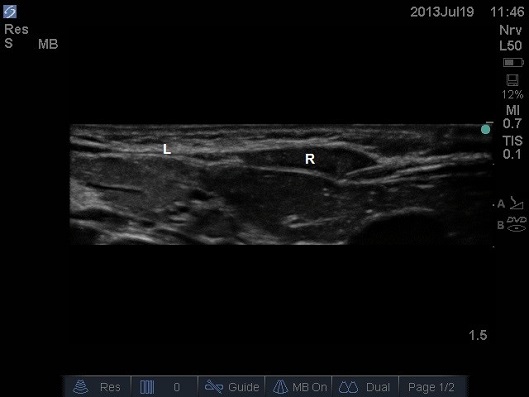

- Insert the block needle in-plane, the puncture point should be suitably lateral that the needle will have a shallow trajectory.

ULTRASOUND OF NEONATAL ABDOMEN IN TRANSVERSE PLANE. NEEDLE HAS A SHALLOW TRAJECTORY COMING FROM LATERAL TO MEDIAL, AND THE BEVEL IS UPPERMOST. THE ANTERIOR SHEATH IS TENTED. THIS CHILD HAS HEPATOMEGALY SECONDARY TO HEART FAILURE, NOTE THE LIVER DIRECTLY BENEATH THE RECTUS MUSCLE. L – LINEA ALBA (MIDLINE), R – RECTUS MUSCLE (NOTE HOW THIN THE MUSCLE IS IN THE NEONATE, APPROXIMATELY 2MM THICK)

- Note it can be difficult to puncture the skin, either lift the skin and push the needle through or make a knick in the skin using a sharp bevelled needle.

- Aim to position the tip of the needle between the rectus abdominis muscle and the posterior rectus sheath.

- Stop the needle tip just superficial to the first white line (the posterior sheath) as a ‘pop’ is not felt or seen in all patients.

- Aspirate and inject 0.25-0.5mls, if the tip is in the correct plane the muscle is peeled off the posterior sheath. If the needle tip remains too superficial then an intramuscular injection occurs; then the needle is carefully advanced.

- The tissues are often quite tough even in a neonate; therefore a steady pressure may be required.